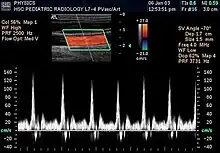

- Modo Doppler: Este modo hace uso del efecto Doppler, para visualizar el flujo sanguíneo.

- Doppler color: La información sobre la velocidad y dirección del flujo en tiempo real se representa con unidades de color.[23]

- Doppler espectral: En vez de utilizar colores, muestra la circulación de la sangre en un gráfico. Se puede utilizar para mostrar el nivel de bloqueo de un vaso sanguíneo.[23]

- Doppler dúplex: Utiliza ecografía convencional para formar imágenes de los vasos sanguíneos y los órganos, las cuales serán convertidas posteriormente en un gráfico similar al Doppler espectral.[23]

- Doppler de onda continua: En esta prueba, las ondas sonoras se envían y reciben de forma continua. Permite medir de manera más precisa la sangre que fluye con mayor rapidez.[23]

La ecografía doppler o simplemente eco-Doppler es una variedad de la ecografía tradicional, basada por tanto en el empleo de ultrasonidos, en la que aprovechando el efecto Doppler, es posible visualizar las ondas de velocidad del flujo que atraviesa ciertas estructuras del cuerpo, por lo general vasos sanguíneos, y que son inaccesibles a la visión directa.[24] La técnica permite determinar si el flujo se dirige hacia la sonda o si se aleja de ella, así como la velocidad de dicho flujo. Mediante el cálculo de la variación en la frecuencia del volumen de una muestra en particular, por ejemplo, el de un flujo de sangre en una válvula del corazón, se puede determinar y visualizar su velocidad y dirección. La impresión de una ecografía tradicional combinada con una ecografía Doppler se conoce como ecografía dúplex.[1]

La información Doppler se representa gráficamente con un Doppler espectral, o bien como una imagen usando Doppler direccional o un power Doppler (Doppler no-direccional). La frecuencia Doppler cae en el rango audible y puede escucharse utilizando altavoces estéreo, produciendo un sonido pulsátil distintivo.